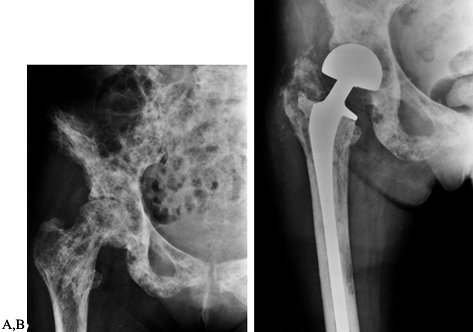

destructive lesions and in most pathologic fractures in which we do not

believe that we can obtain rigid fixation with closed rodding (Fig. 130.1). The rodding procedure is exactly the same as for closed rodding with the following modifications.

![]() |

|

Figure 130.1. Anteroposterior radiograph of the proximal humerus showing a purely lytic lesion with a pathologic fracture. B:

Anteroposterior radiograph following open reduction internal fixation with an intramedullary rod augmented with methyl methacrylate. Note the mature periosteal healing around the cement augmentation. |